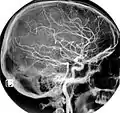

Angiografie prin rezonanță magnetică

Arteriografie carotidă normală